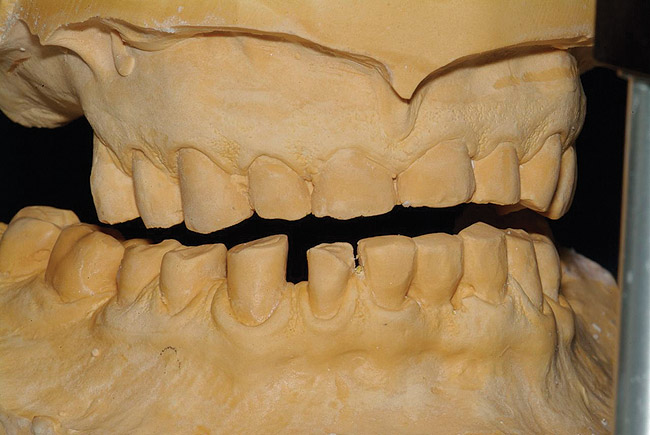

Figure 1  The proposed gingival alteration marked on the cast.

Figure 1

Figure 2   Laboratory alteration of the gingival contours in the diagnostic wax-up.

Figure 2

3. Lack of Direction on Tooth Positioning and Gingival Alteration

Practitioners must inform the laboratory of the proper amount of incisal edge addition. This decision must be made in the operatory during repose, smiling, and speaking. Robbins has outlined many of these principles.17 These are not static choices that can be made on mounted casts. While photographs of the patient are important for the laboratory, the ultimate decision should rest with the restorative dentist. In addition, if surgical alteration of the gingival architecture is planned, clinicians should mark proposed surgical alteration of the gingival levels on the casts. The laboratory can adjust the stone to mimic the change on the diagnostic wax-up (Figure 1 and Figure 2).